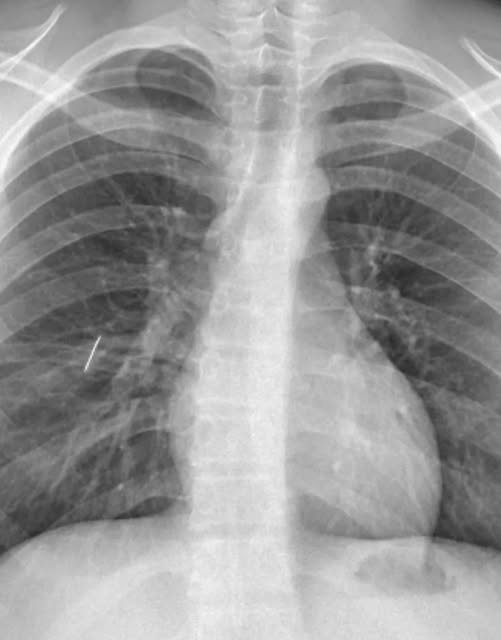

Un equipo médico del Hospital Interzonal San Juan Bautista logró extraer con éxito una aguja alojada en el pulmón de un joven derivado desde Tinogasta.

Tras un trauma penetrante de tórax, el paciente fue sometido a una cirugía abierta de una hora y media, ya que la ubicación del objeto impedía la expansión pulmonar.

El procedimiento destacó por el uso de una técnica de intubación selectiva mediante fibrobroncoscopio, que permitió ventilar un solo pulmón y trabajar con mayor precisión sobre el área afectada.

El Dr. Fernando Lestussi, encargado de la operación, resaltó que la intervención debió resolverse localmente debido al alto riesgo que suponía un traslado.